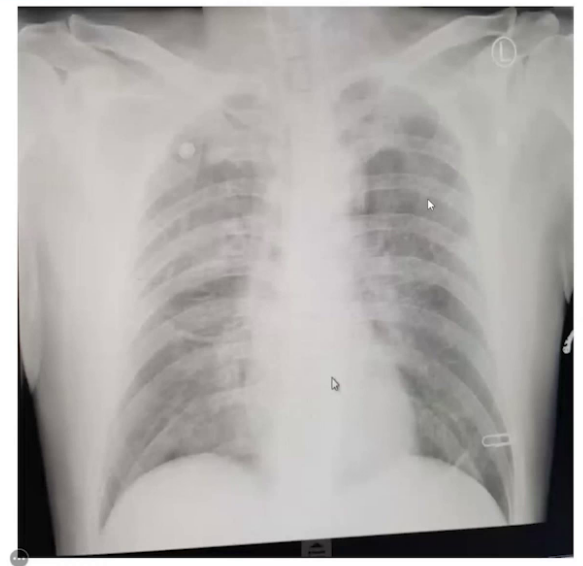

3.术后转归:转入ICU后当天查血气、心肌酶血指标及心脏超声均正常,胸片显示双肺肺水肿表现。术后第2天患者循环稳定,血管活性药停止泵入,下午16点拔除气管插管,第3天返回普通病房,第6天顺利出院。